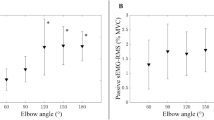

The SWE measurements listed in Table 3 identified significant differences (p < 0.001) during the resting position for all the tested lower limb muscles and the BB. The SWV was higher in the passively stretched position in the quadriceps. However, it did not result in significant differences amongst the age groups. The results can be better appreciated graphically in the clustered error bars in Fig. 2 during the resting position and in Fig. 3 during the passive stretching position.

The mean SWV difference between the middle-aged and young groups over all muscles was − 4.1% ranging from 0.5 to − 7.3%. As for the elderly and middle-aged, the mean difference was − 12.9% and ranged from − 6.5 to − 18.8%. However, the highest mean difference of − 16.5% was observed between the elderly and young groups with the differences amongst the muscles ranging from − 11.0 to − 23.3%. The VI and BB exhibited the smallest differences, whereas the VM and SM were the highest.

Despite the gradual decreasing SWV across almost all muscle, the post hoc analysis revealed that only the VL had a significantly decreasing SWV between all three age groups. The other muscles were only significantly lower in the elderly participants (p < 0.001) compared to the other two groups. SWE examples are shown in Fig. 4.